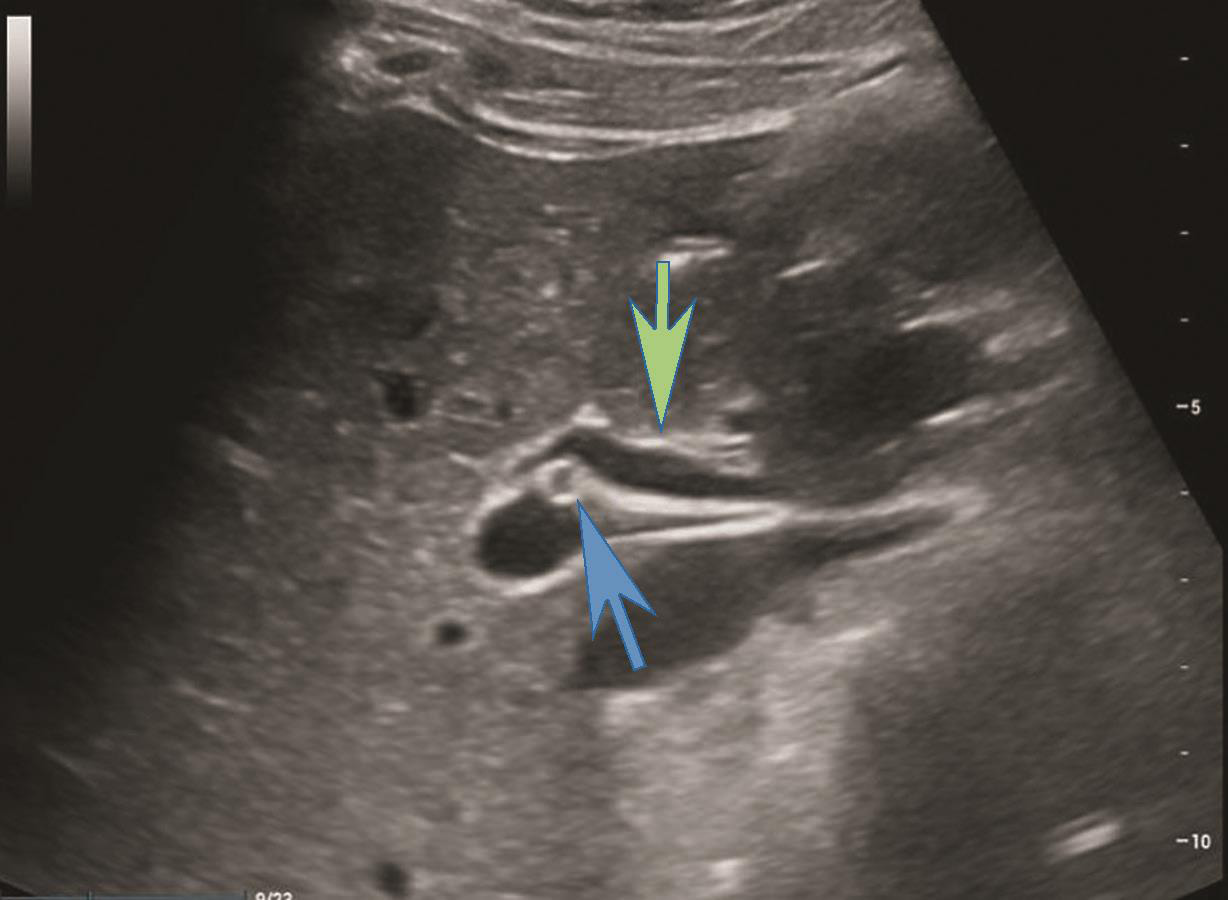

(4)肝门部肝外胆管上段灰阶超声图像及CDFI图像(图2-1-2,图2-1-3)。

(5)肝外胆管下段长轴切面灰阶超声图像(图2-1-4)。

图2-1-2 肝门部肝外胆管上段灰阶超声图像

图示绿色箭头所示为肝外胆管上段,蓝色箭头所示圆形管状结构为肝动脉的横断面

图2-1-4 肝外胆管下段灰阶超声图像

箭头所示为胰头后方肝外胆管下段长轴切面